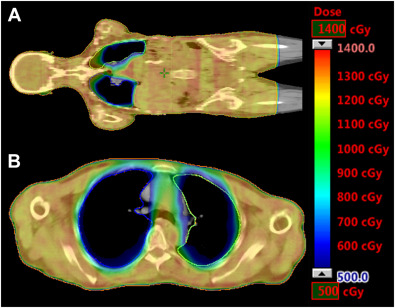

Int J Radiat Oncol Biol Phys. 74: 831-836Witt J.S. Rosenberg S.A. Bassetti M.F.

MRI-guided adaptive radiotherapy for liver tumours: visualising the future.

Lancet Oncol. 21: e74-e82Bohoudi O. Bruynzeel A.M.E. Senan S. et al.

Fast and robust online adaptive planning in stereotactic MR-guided adaptive radiation therapy (SMART) for pancreatic cancer.

Radiother Oncol. 125: 439-444Green O.L. Henke L.E. Hugo G.D.

Practical Clinical Workflows for Online and Offline Adaptive Radiation Therapy.

Semin Radiat Oncol. 29: 219-227Mittauer K. Paliwal B. Hill P. et al.

A New Era of Image Guidance with Magnetic Resonance-guided Radiation Therapy for Abdominal and Thoracic Malignancies.

Cureus. 10: e2422Rosenberg S.A. Henke L.E. Shaverdian N. et al.

A Multi-Institutional Experience of MR-Guided Liver Stereotactic Body Radiation Therapy.

Adv Radiat Oncol. 4: 142-149Feldman A.M. Modh A. Glide-Hurst C. et al.

Real-time Magnetic Resonance-guided Liver Stereotactic Body Radiation Therapy: An Institutional Report Using a Magnetic Resonance-Linac System.

Cureus. 11: e5774Henke L.E. Olsen J.R. Contreras J.A. et al.

Stereotactic MR-Guided Online Adaptive Radiation Therapy (SMART) for Ultracentral Thorax Malignancies: Results of a Phase 1 Trial.